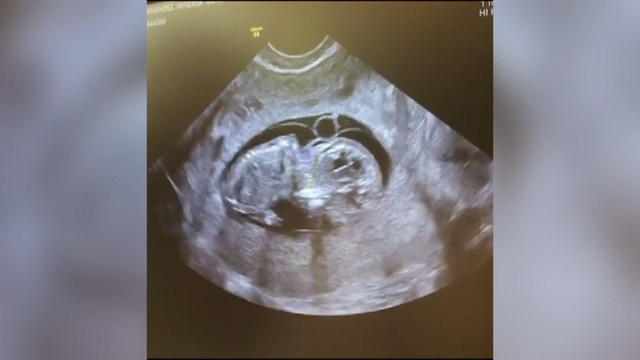

Barrie Drewitt-Barlow, bebeğin videosunu sosyal medya hesabından paylaştı. Barlow, sosyal medya hesabından yaptığı paylaşımda bebeklerinin bir ay erken doğduğunu ve isminin Valentina Willow Drewitt-Barlow olduğunu duyurdu.

Sosyal medya hesaplarından bebeğin videosunu paylaştı. Barrie paylaşımında, "Güzel kızımız Valentina Willow Drewitt-Barlow dünyaya hoş geldin. Kızımız neredeyse bir ay erken doğdu ama yine de mükemmel. Tamamen kutsanmış hissediyoruz. Seni Seviyorum Scott" ifadelerini kullandı.